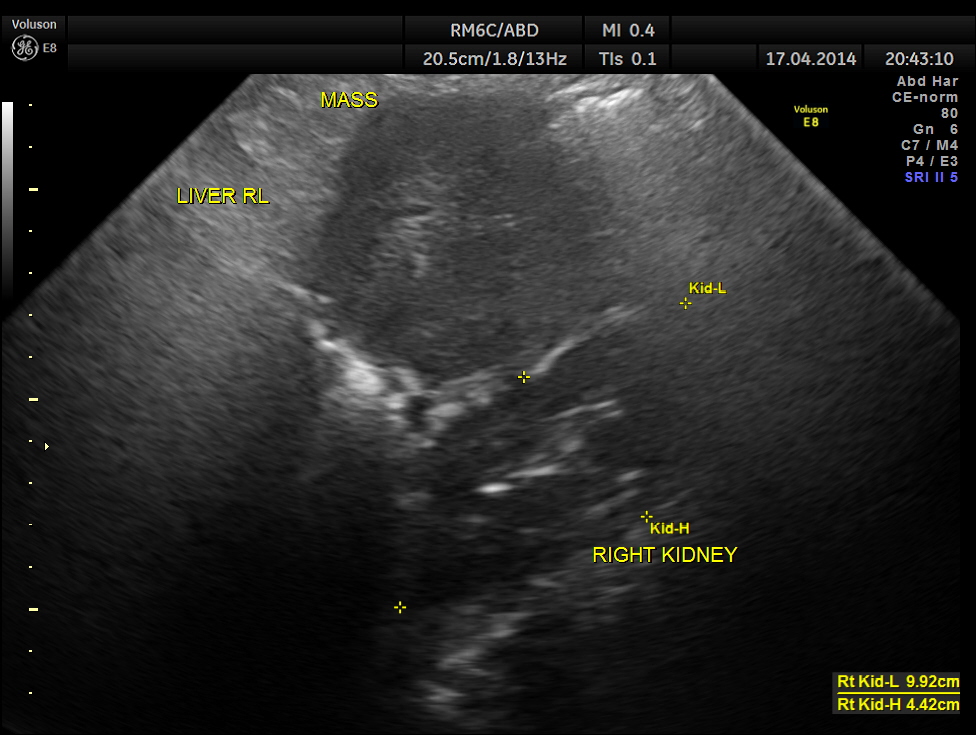

Two distinct mass lesions were seen in the right side of the abdomen in the lumbar and hypochondriac regions . Though they appeared distinct from the liver , it was a bit confusing.

Thw two masses seen out of the uterus and mainly in the right upper quadrant are shown below.

The ultrasound gave us a few inconclusive findings . Uterus was massively enlarged ; a large fibroid was seen ; adenomyosis was seen ; endometrium was thickened ; two large mass lesions were seen in the right upper quadrant and right lumbar region . But it was difficult to ascertain the origin of these extra uterine masses .